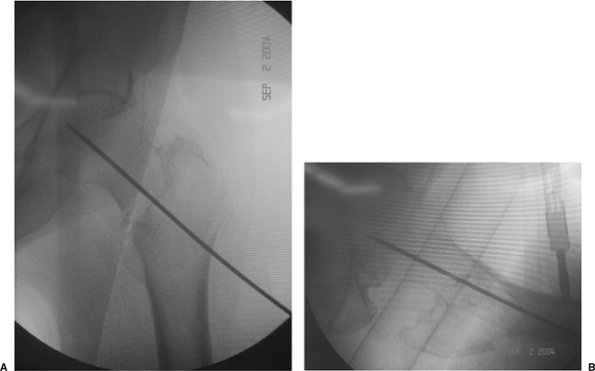

Using image intensification, a guide pin is inserted into the femoral

neck and head using an angle guide. Most commercially available

sliding-hip screws are available in plate angles of from 125 to 155

degrees, of which the 135- and 150-degree devices are the most popular.

I usually select a 135-degree device because its use facilitates lag

screw placement into the desired central portion of the femoral head,

and because of its entry point in metaphyseal cancellous bone, it

decreases the stress riser effect of a higher-angle device.

insertion into the femoral neck and head using either an angle guide or

freehand technique with later adjustment of the plate to accommodate

the selected angle. I prefer to use the angle guide because it helps

ensure placement of the guide pin at the desired 135 degree angle and

to a check to proper fracture reduction; inability to place the guide

pin into the center of the femoral head and neck using this angle

should alert the surgeon to the possibility of a fracture malreduction.

in the center of the femoral head and neck on both the AP and lateral

planes within 5 to 10 mm of the subchondral bone (Fig. 16.10).

Central and deep placement allows lag screw purchase in the best bone

available as well as allows maximal collapse of the screw before its

threads engage the plate barrel.

![]() |

Figure 16.10. A. AP and (B) lateral image-intensifier radiographs of the inserted guide pin.